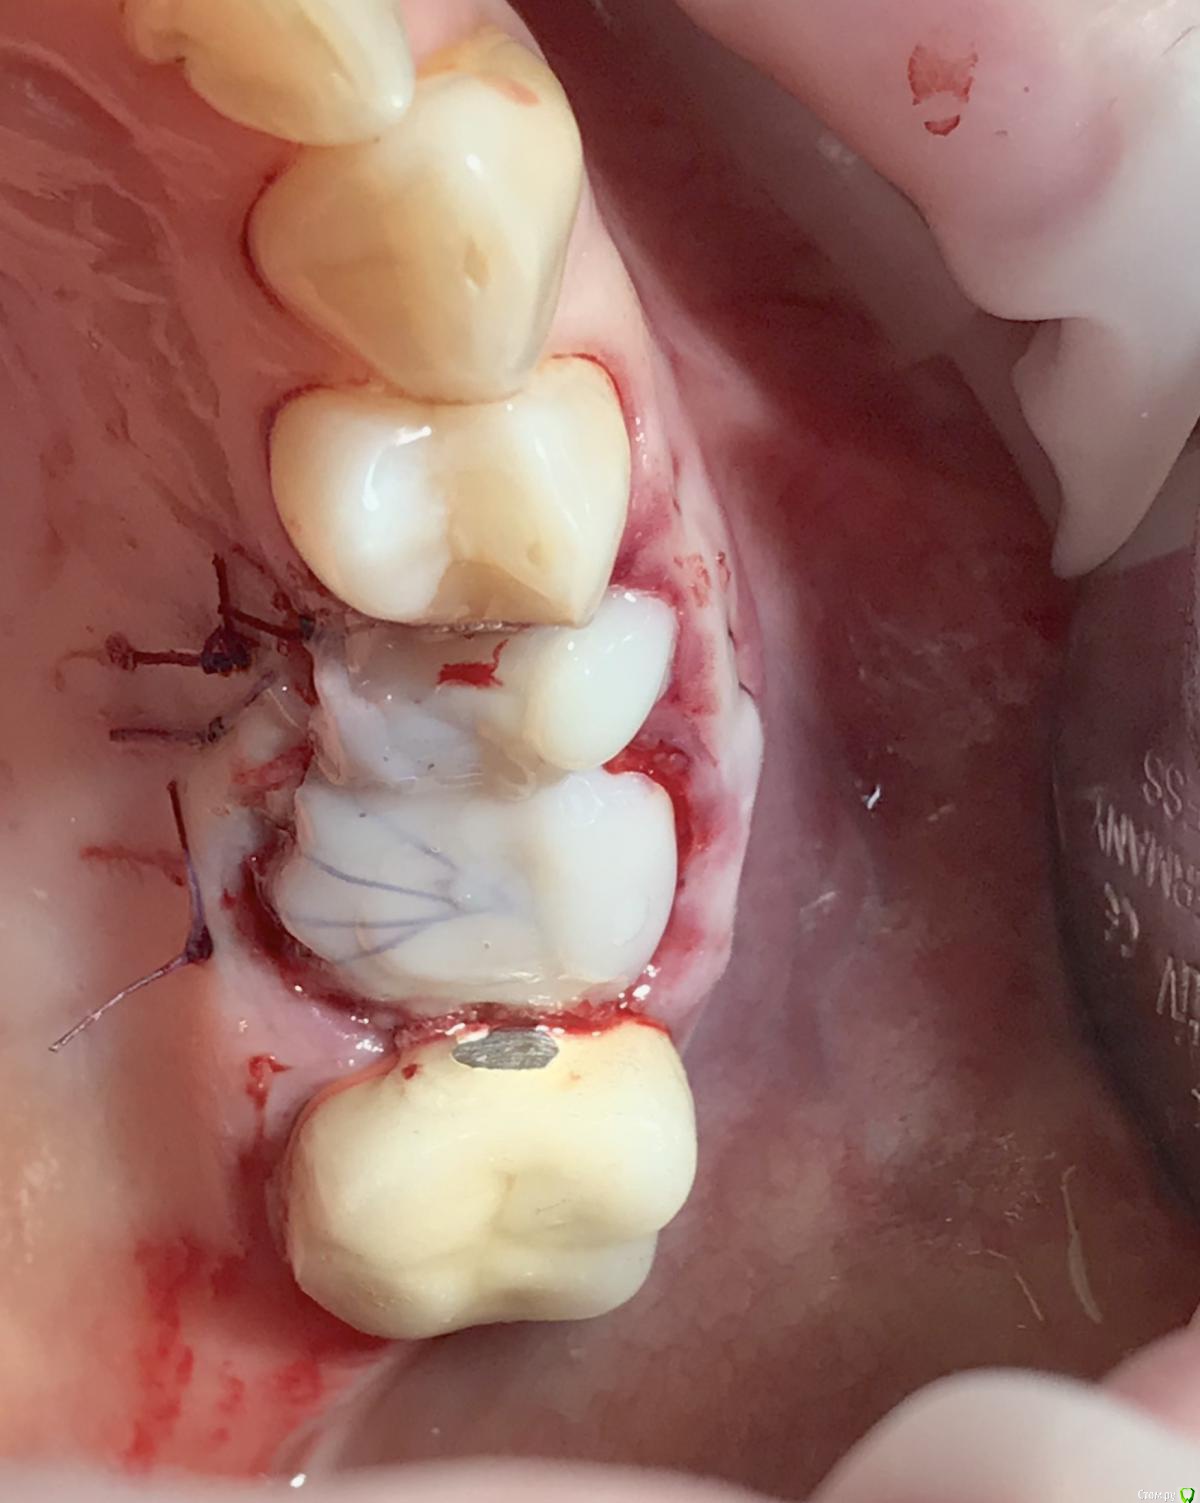

колесников Опубликовано 29 апреля, 2019 Поделиться Опубликовано 29 апреля, 2019 Модифицированый Ноймайер. Без радикса. Или это уже самостоятельный метод? Ссылка на комментарий

Дмитрий Л. Опубликовано 29 апреля, 2019 Поделиться Опубликовано 29 апреля, 2019 Защитная повязка. Ссылка на комментарий

колесников Опубликовано 29 апреля, 2019 Поделиться Опубликовано 29 апреля, 2019 Не только. С ее помощью можно получить прирост мягких тканей,подтянуть зенит. Ссылка на комментарий

Дмитрий М Опубликовано 1 мая, 2019 Поделиться Опубликовано 1 мая, 2019 (изменено) Модифицированый Ноймайер. Без радикса. Или это уже самостоятельный метод? из какого материала? по фото видно вы не фиксируете ее между соседних зубов! только на швах держится? на 2-3 день она просто будет висеть (болтаться) на нитках!? смысл Ноймайера - связка корня, которая срастается с маргинальной деснойа в данном случае каков механизм действия? как автор методики, расскажите подробнее Изменено 1 мая, 2019 пользователем Дмитрий М Ссылка на комментарий

колесников Опубликовано 1 мая, 2019 Поделиться Опубликовано 1 мая, 2019 (изменено) Да вы правы,нужна связка. Вначале я использовал Колапол,но его хватало на неделю,потом все начинало дурно пахнуть. Однажды заметил что Альвастаз губка в герметично закрытой ране ,неведомым образом слипается с сдесневымиистенками лунки,да так плотно что трудно отделить и при этом сохраняет плотноэоастическую структуру. Как подтянуть мягкие ткани . Назовём это быстрый Ноймайер. В лунке имплант с широким но коротким фдм (или не коротким,край фдм должен быть в ровень или на 1мм ниже десневого края) . На спрессованный фрагмент Альвастаза наносим жидкотекучий композит,размером по форме лунки,но 1-2мм меньше,толщиной 2мм. Укладываем на фдм. Далее п-образными швами крест на крест придавливаем пробку вниз и соответственно десневой край подтягивается вверх. Если зашивать через край,фрагмент придавливается,но десна не подтягивается.Чем толще пробка,тем больше подтянуть можно,но и напряжение от швов больше,есть угроза прорывание. С шайбой из корня, если так делать, получается очень глубокая шахт с тонкими десневыми стенками,мне как то не понравилось. Фиксировать можно и к соседним зубам,но это не всегда возможно и это если на длительный срок. На швах достаточно 3-4ех недель если для консервации,2-3 если на фдм.После ушивания ещё заливаем сверху композитном,чтобы зафиксировать швы и перекрыть щели по периметру. Изменено 1 мая, 2019 пользователем колесников 1 Ссылка на комментарий